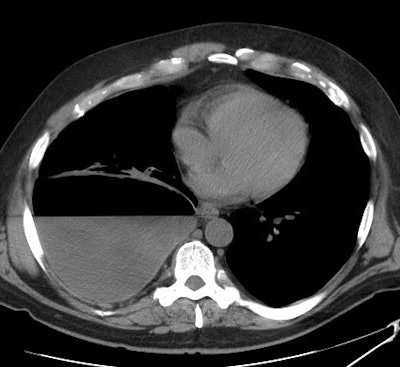

Computed tomography: On CT empyemas are usually oblong,

have

a sharp interface with the lung parenchyma and displace vessels

and

bronchi

away from the empyema. Following contrast administration, there is

enhancement of the abnormally thickened parietal

and visceral pleura which are separated by the empyema ("split

pleura

sign") [6]. The split pleura sign can be seen in 68-86% of

patients

with empyema, however, it is not specific for the condition as it

can

be seen in other causes of exudative effusion as well (malignant

effusion, hemothorax, prior pleurodesis) [8,9]. Increased

density within the extrapleural fat may also be seen. The presence

of a loculated (non-dependent) pleural fluid collection in a

patient

with

a pneumonia strongly suggests the presence of an empyema. It is

important

to remember, however, that many empyemas can resemble a simple

parapneumonic

effusion. Gas bubbles in the pleural space is presumptive evidence

of a

bronchopleural fistula, but the finding may also be seen due to

infection

with a gas forming organism or following thoracentesis [4]. A

pleural

peel

appears as a markedly thickened parietal pleura which is separated

from

the chest wall by a thickened layer of extra-pleural fat. Focal or

diffuse

calcification can occur and the volume of the affected hemithorax

is

reduced.

[6]

A non-contrast CT scan on the patient shown above

demonstrated a large

right pleural fluid collection with an air-fluid level.

Thickening of

the underlying pleural surface can be seen even on

non-contrast

imaging. The fluid was infected at aspiration. |